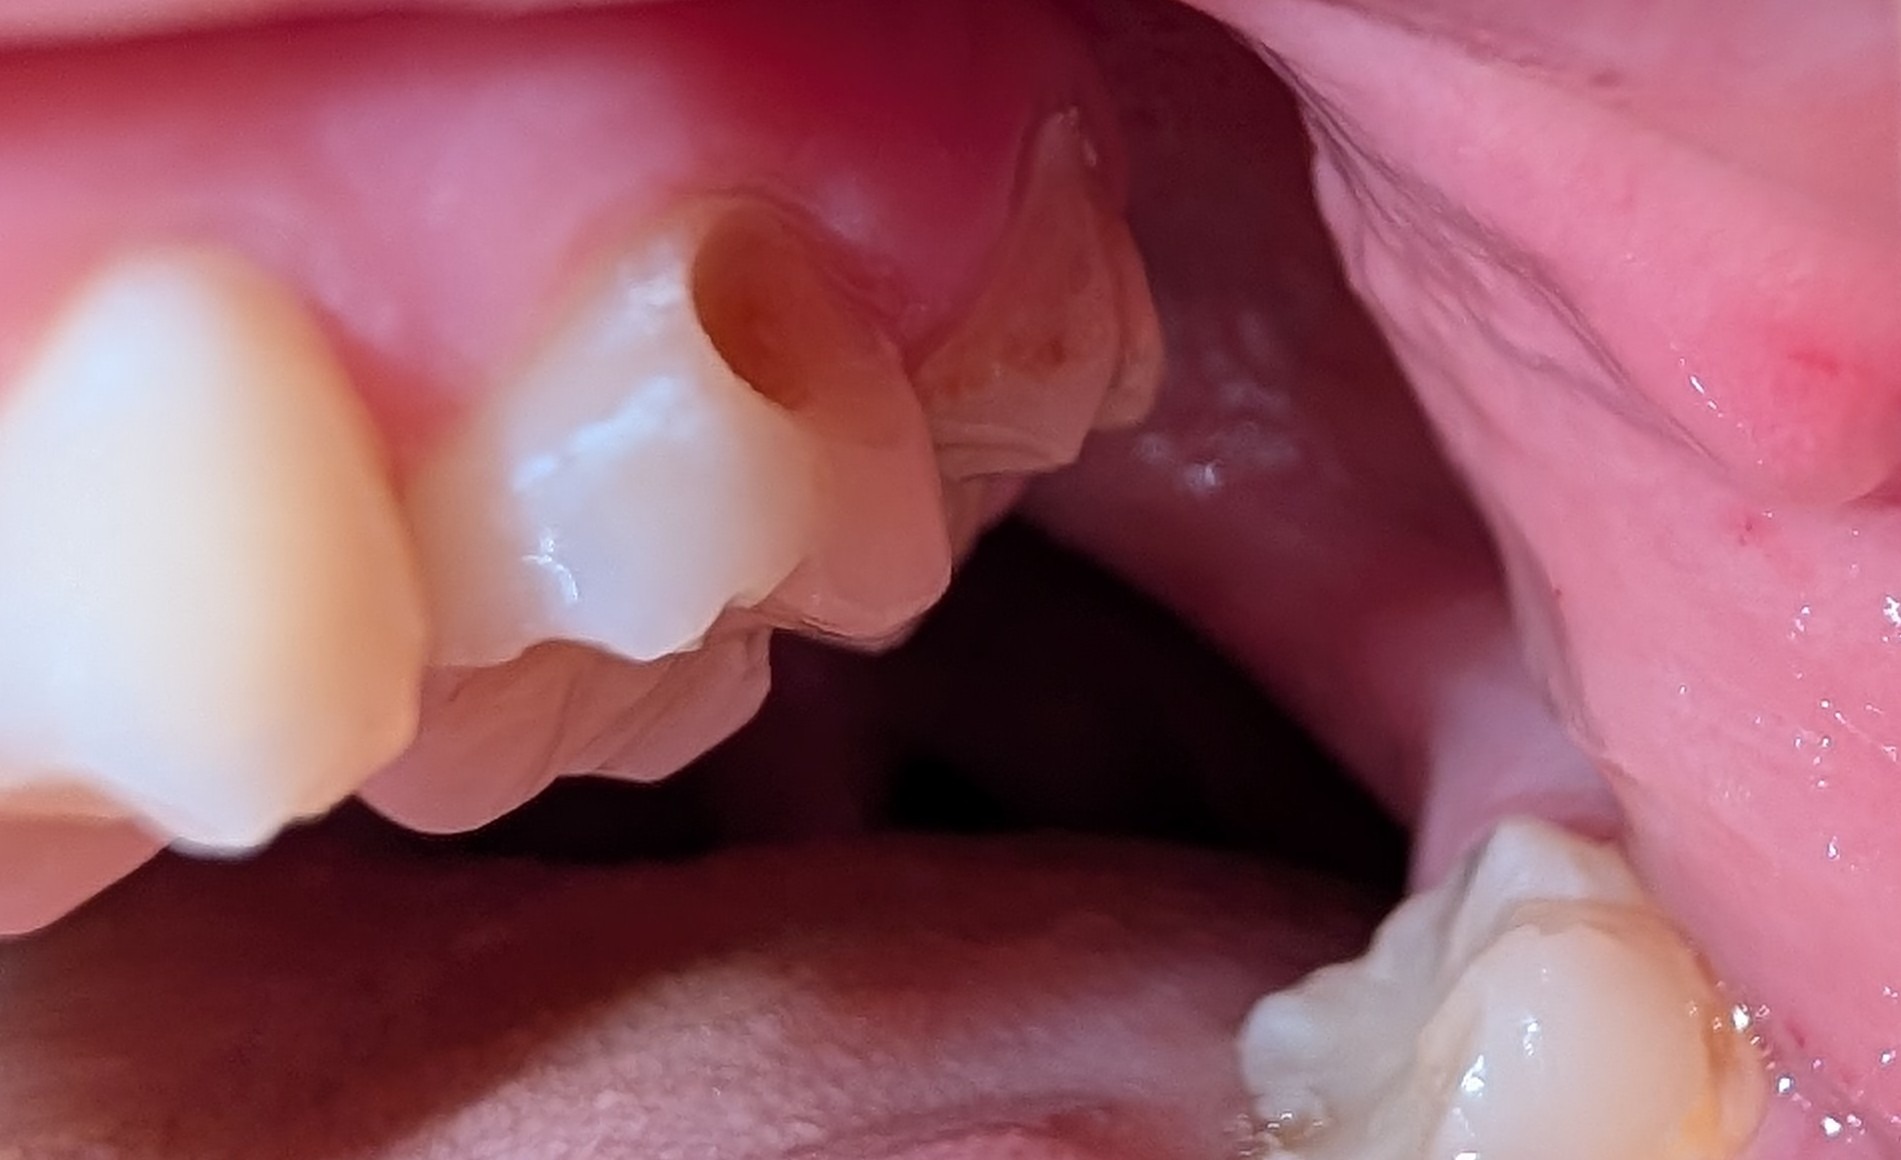

This all started with needing a few fillings and has snowballed into something much much worse. I've already been to the ER with pulpitis once and I couldn't afford it, and I may have to go again. I'm suffering daily headaches and sensitivity and it's hard to enjoy eating or drinking, let alone get out of bed.

I just need some help. I'm trying to get insurance to cover the root canals but they won't budge, and since I can't afford any better insurance and can't get enrolled in my job's insurance until October, it's even harder.